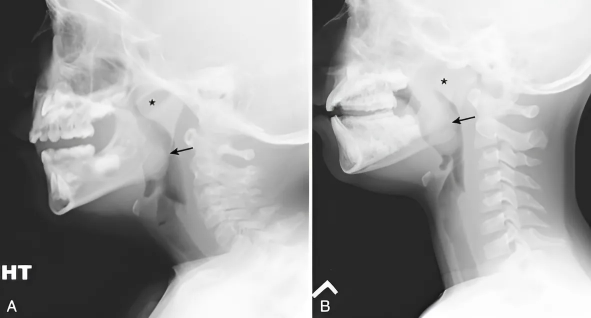

The airway doesn't collapse randomly—it collapses because of specific spinal positioning during sleep.

Stanford University's landmark 2019 study proved it:

When sleep apnea patients were positioned with proper cervical spine alignment, 78% showed normal breathing patterns without any CPAP intervention.

Your airway doesn't collapse because you stop breathing properly.

It collapses because traditional pillows force your cervical spine into an unnatural forward curve, creating a mechanical kink in your airway.

When you lie on a regular pillow, your head tilts forward and down.

This bends your neck at an acute angle, literally kinking your airway closed.

Proper cervical spine elevation maintains your airway's natural opening by preventing the forward head tilt that creates the kink.